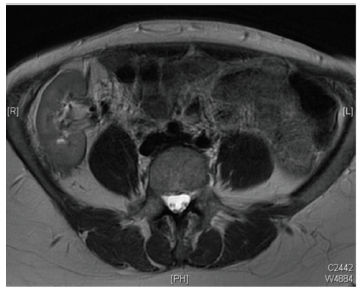

Tacrolimus levels and biochemistry were moni­tored frequently. After an initial sustained rise in creatinine, the level began to decline 6 weeks after transplant along with improvement in urine protein-to-creatinine ratio (Figure 2) and improvement shown in MAG3 renogram imaging. A magnetic resonance imaging scan was carried out at 14 months due to pelvic pain (Figure 3). It revealed no underlying pathology; however, it showed that the solitary kidney had grown in size, measuring 6.8 cm cranio-caudally. The recipient has remained well and currently has stable graft function.